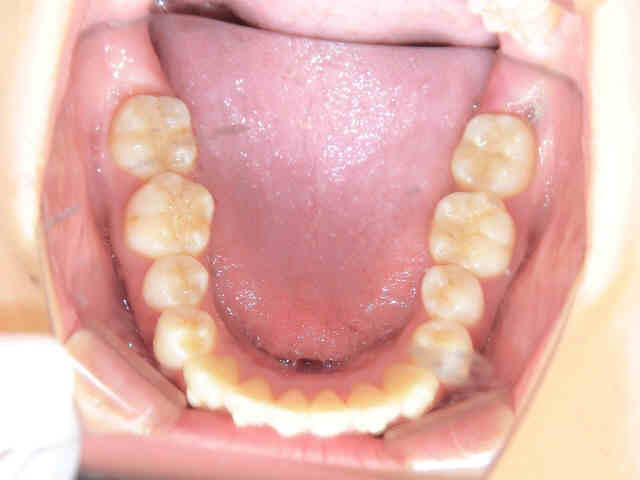

左上の写真は上顎を下から、右上の写真は下顎を上から撮影したものです。右上の黒色矢印部分では、下顎前歯がやや前方へ傾斜している様子が見受けられます。